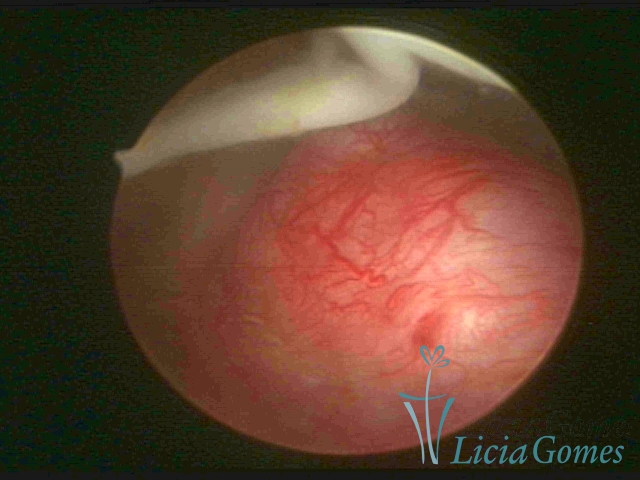

Canal cervical trófico, com o fio de Mirena®